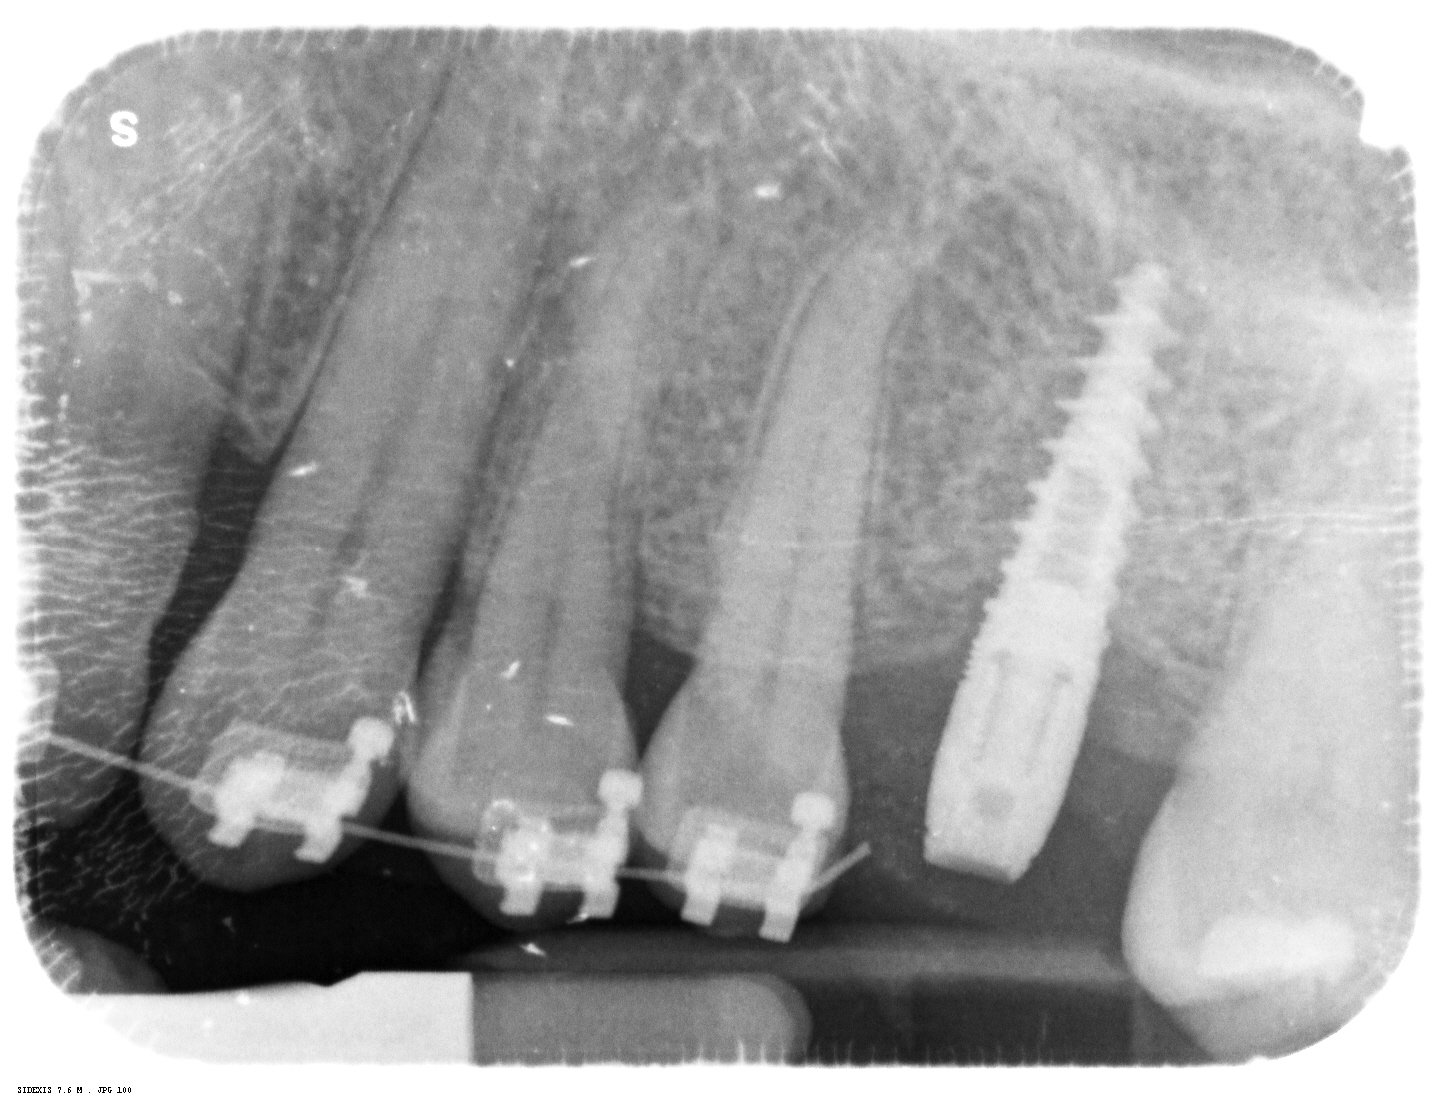

Paciente que acude con implante colocado en posición de 12 en el año 2018 en Tenerife. Viene con una especie de Maryland cementado por lo que no soy capaz de [...]